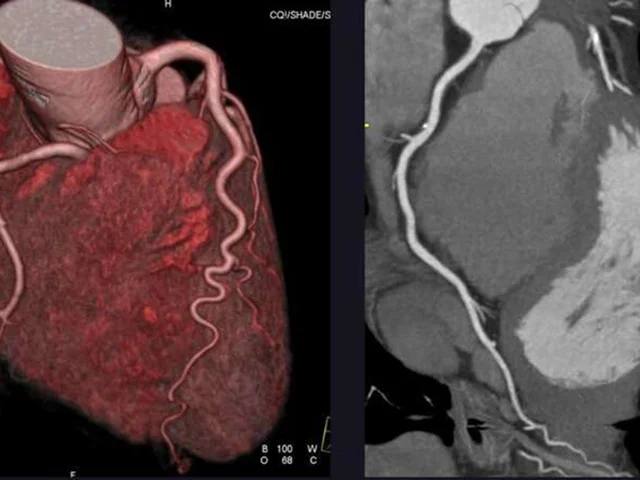

CT or Invasive Coronary Angiography in Stable Chest Pain

NEJM   Evaluating Stable Chest Pain — An Evolving Approach